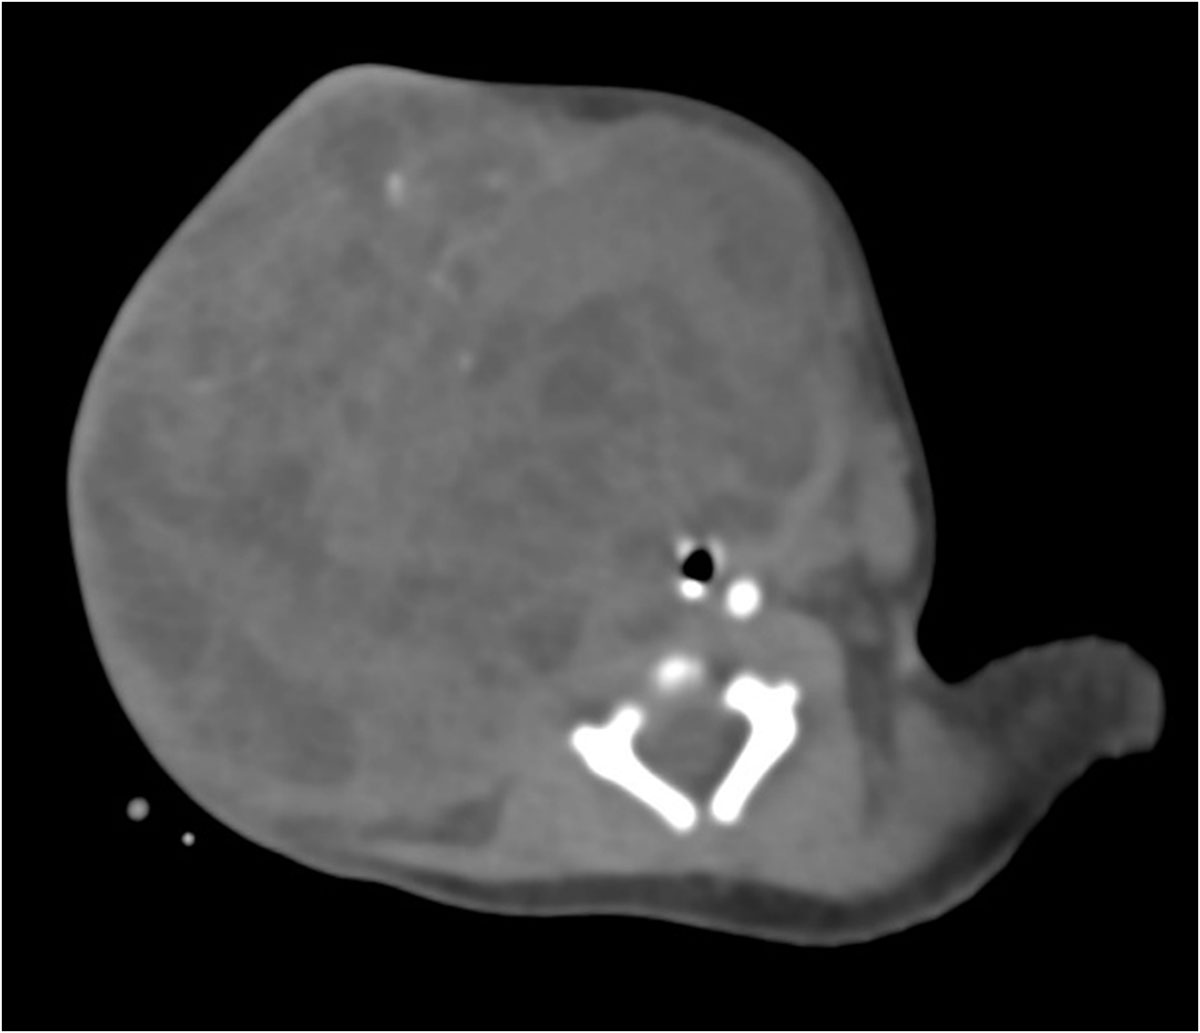

Se identifica imagen redondeada, de bordes lobulados, dependiente de tejidos blandos, heterogénea por áreas sólidas y quísticas internas, así como algunas calcificaciones irregulares dispersas, tras la aplicación de medio de contraste con realce ávido heterogéneo en sus porciones sólidas, con dimensiones de 89.3×88.3×80.9 mm y volumen de 333.6 cc; localizada en los espacios masticador, parotídeo, parafaríngeo, submandibular, visceral, supraesternal, perivertebral bucal y cervical posterior derechos.5. IMÁGENES

El teratoma cervical es una neoplasia congénita rara, derivada de células germinales pluripotenciales que contienen tejidos de las tres capas embrionarias. Representa menos del 5% de los teratomas pediátricos y su localización en el cuello puede ocasionar compromiso de la vía aérea, constituyendo una urgencia neonatal potencialmente mortal.

La tomografía computarizada (TC) muestra una masa compleja bien delimitada, con componentes sólidos, quísticos, calcificados y grasos, hallazgo característico de los teratomas maduros. La TC permite valorar la relación con estructuras vasculares, la vía aérea y el mediastino, siendo útil en la planificación quirúrgica.